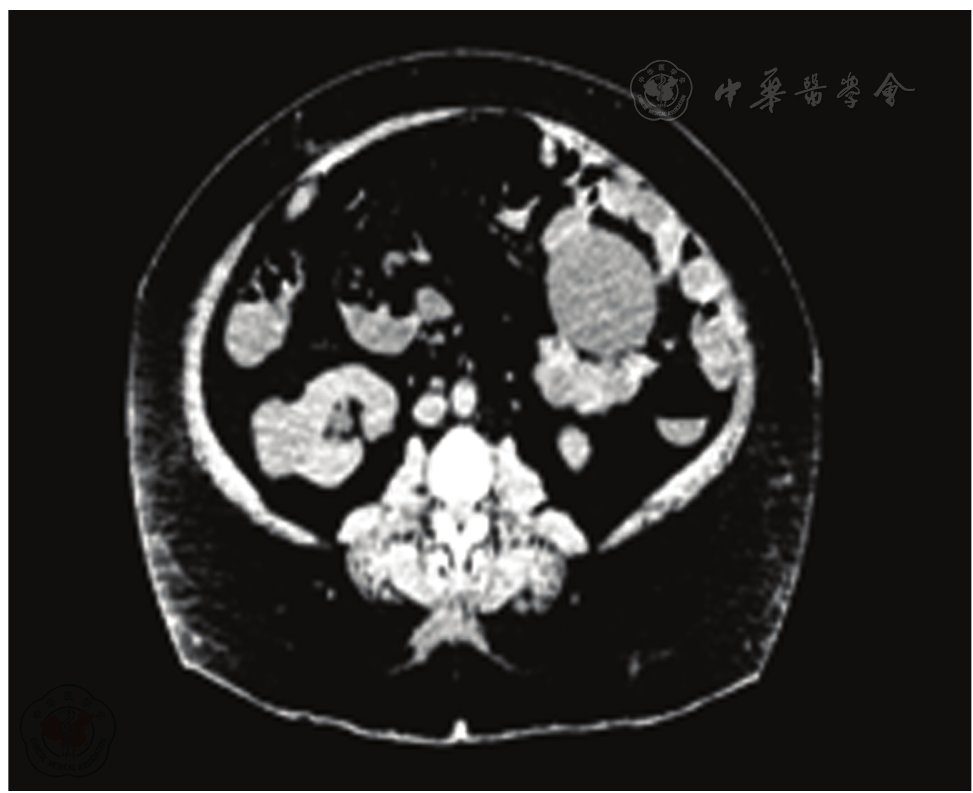

图1 2017年2月17日双肾CT